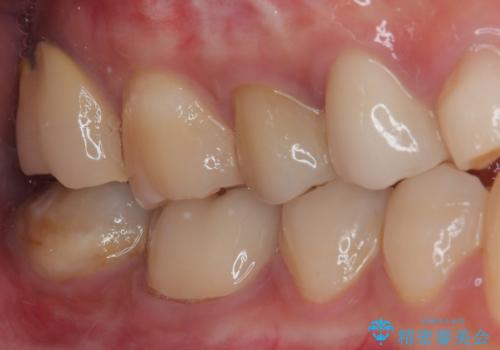

病変が消退しているかどうか、半年、1年とレントゲン写真で経過観察を行う必要があります。

海外に行かれていた都合で、術後2年での経過観察となりましたが、無事に病変の消失が認められました。